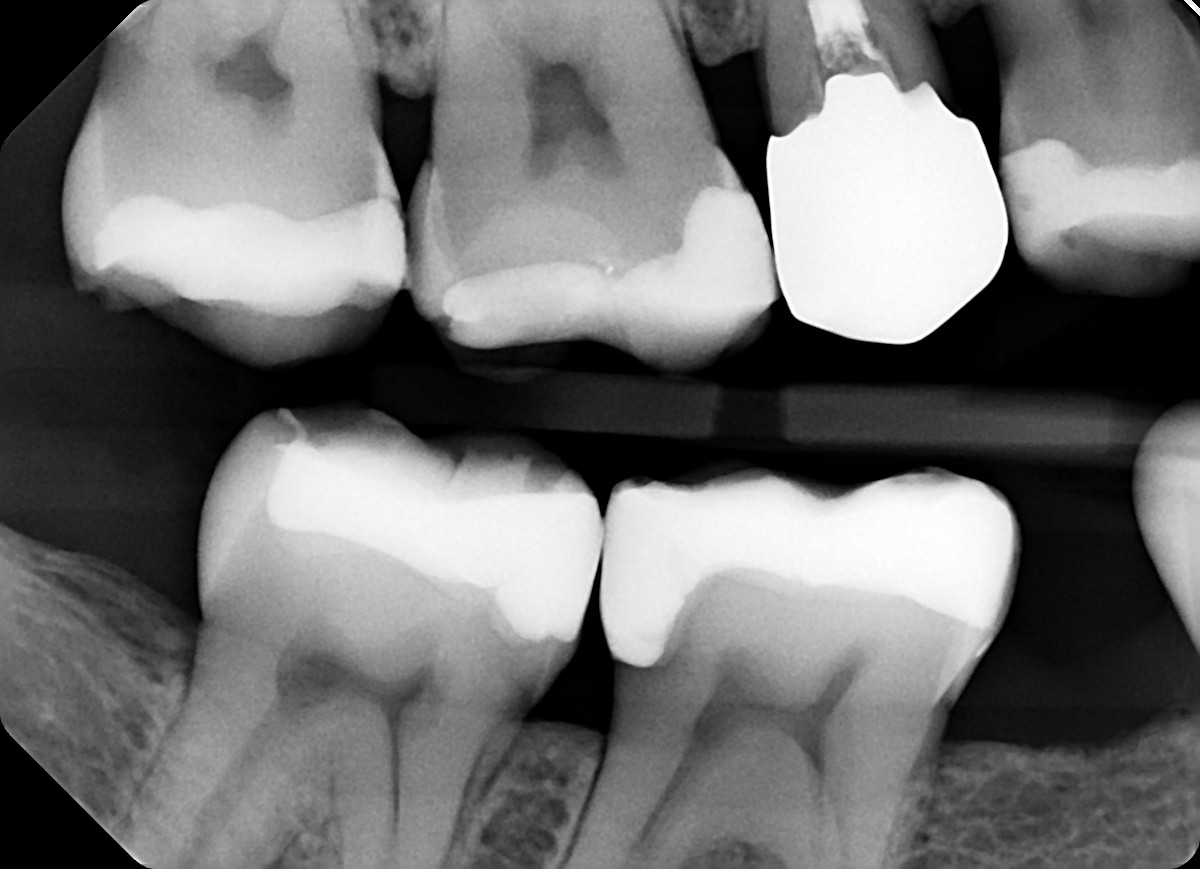

6. On which surface a recurrent caries can be detected?

7 / 35

7. On which surface a recurrent caries can be detected?

No cavity can be detected, restorations on 1.7, 4.6 and 4.7 are porcelain onlays